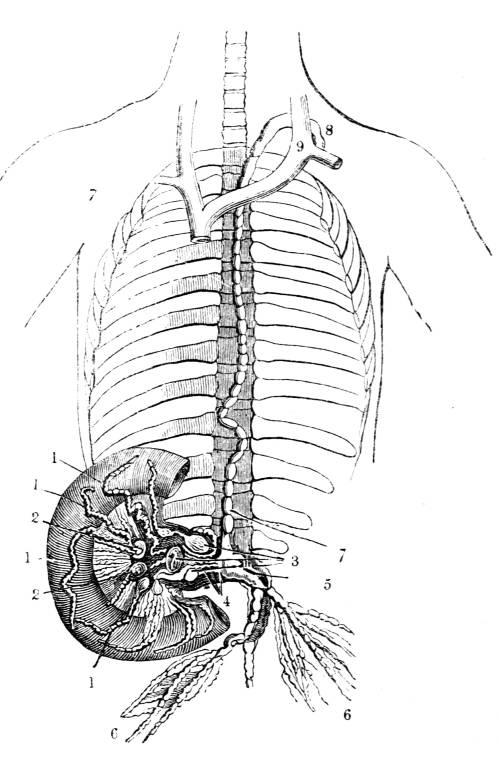

1. The trachea. 2. The right and left bronchus; the left

bronchus showing its division into smaller and smaller

branches in the lung, and the ultimate termination of the

branches in the air vesicles. 3. Right auricle of the heart.

4. Left auricle. 5. Right ventricle. 6. The aorta arising from

the left ventricle, the left ventricle being in this diagram

concealed by the right. 7. Pulmonary artery arising from

the right ventricle and dividing into, 8. The right, and

9. The left branch. The latter is seen dividing into smaller

and smaller branches, and ultimately terminating on the

air vesicles. 10. Branches of one of the pulmonary veins

proceeding from the terminations of the pulmonary artery

on the air vesicles, where together they form the net-work

of vessels termed the Rete Mirabile. 11. Trunk of the

vein on its way to the left auricle of the heart. 12.

Superior vena cava. 13. Inferior vena cava. 14. Air vesicles

magnified. 15. Blood-vessels distributed upon them.

48

371. Such is the structure of the vessel that

carries the air to the blood, and such is the mode

of its distribution.

The vessel that conveys the blood to the air

is the pulmonary artery, the great vessel which

springs from the right ventricle of the heart (fig.

CXL. 5).

The pulmonary artery soon after it issues

from the right ventricle of the heart divides into

two branches (fig. CXL. 7, 8, 9), one for each

lung (fig. CXL. 8, 9). Each branch of the pulmonary

artery as soon as it enters its corresponding

lung (fig. CXL. 9) divides and ramifies

through the organ in a manner precisely similar

to the bronchial tubes. Every branch of the

artery is in contact with a corresponding branch

of the bronchus (fig. CXL. 2), divides as it divides,

and accurately tracks its course throughout (fig.

CXL. 2), until the ultimate divisions of the artery

at length reach the ultimate vesicles of the bronchus

(fig. CXL. 2, 10), upon the delicate walls of

which the capillary arteries rest, expand, and

ramify, forming a net-work of vessels, so complex

that the anatomist who first observed it, named it

the Rete Mirabile, the wonderful net-work, and49

it is still called the Rete Mirabile Malpighi, or

the Rete Vasculosum Malpighi (fig. CXL. 2, 9,

10).

372. The blood which has finished its circulation

through the system, returned by the great

systemic veins (fig. CXL. 12, 13), to the right side

of the heart (fig. CXL. 3), is driven by the right

ventricle (fig. CXL. 5), into the pulmonary artery

(fig. CXL. 7); by the branches of which (fig.

CXL. 8, 9) it is distributed to the air vesicles

of the lungs: consequently the right heart of

man bears precisely the same relation to the

lungs, that the single heart of the fish bears to the

branchiæ; the former is a pulmonic, as the latter

is a branchial heart; one half of the double heart

of the more highly organized creature is employed

to circulate the venous blood of the system

through the lungs, as the whole of the single heart

of the less highly organized animal, is employed to

propel the blood through the branchiæ (368).

From the capillary branches of the pulmonary

artery in the Rete Mirabile (fig. CXL. 9), arises

another set of vessels termed the pulmonary veins

(fig. CXL. 10), which receive the blood from the

venous vessels spread out on the air vesicles: for

the pulmonary artery is functionally a vein, since

it contains venous blood, though it is nominally an

artery because it carries blood from the heart (269);

and in like manner the pulmonary veins are func50tionally

arteries since they contain arterial blood,

though they are nominally veins because they

carry blood to the heart (272). The branches of

the pulmonary arteries are larger in size and

greater in number than those of the pulmonary

veins, the reverse of what is observed in any other

part of the body; because the pulmonary artery

contains the blood which is to be acted upon by

the air, while the pulmonary veins merely receive

the blood which has been acted upon by the air,

and the former ramifies more minutely than the

latter, in order that the air may act on a larger

surface of blood.

373. In the Rete Mirabile the junction of the